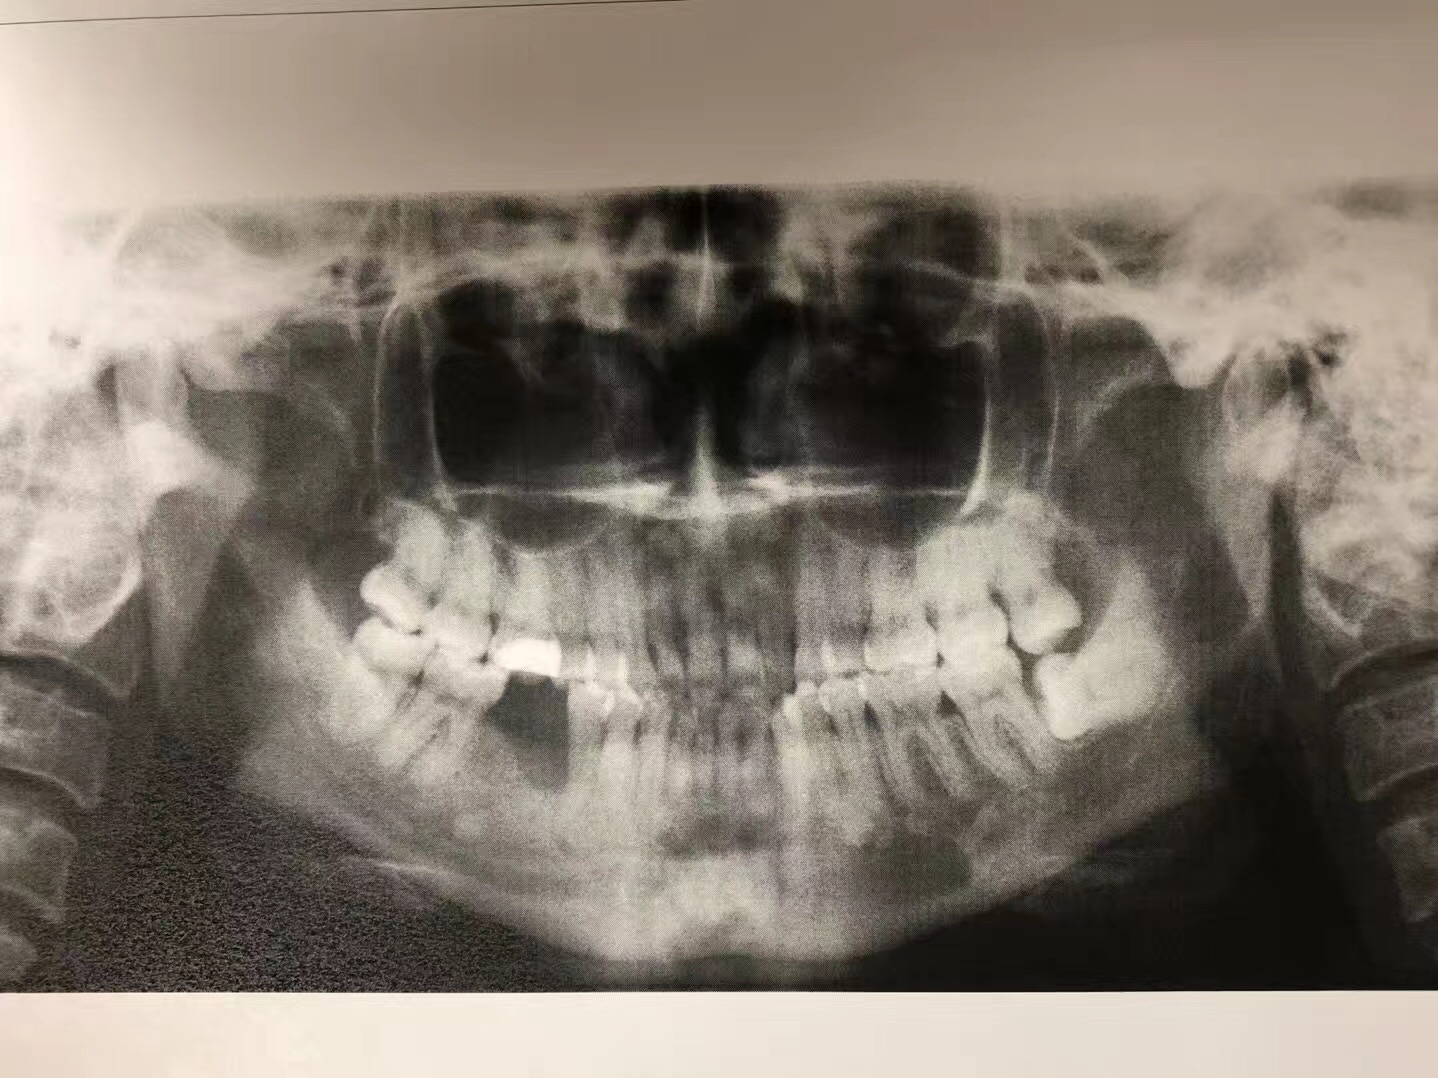

2016年,她感觉第一大臼齒的地方很疼痛去看了一般的牙醫,这位牙醫立即幫她拔了疼痛的牙齒,结果她的牙根却留在牙糟裏。后來,她来到我們南加大醫院的口腔外科,我的住院醫生见状,幫她把牙根拔了,結果引起骨壞死。这一年多来,住院醫生只有開消炎藥和漱口水給她,但一直未见好转,后来,住院醫生把这位患者病情告诉我,希望我能幫她。我了解病情后,若按照常规治疗,效果不明显。我采用了自己研發的新藥,第一次病人需要在诊所注射,之後,再把藥交給病人,譲病人携帶回家自己打。二個星期後,病人回診,骨頭已經好了,而且還長的和之前一样。她见到我激动的说,林医生是我的救命恩人。

今年,我研制治療骨壞死的藥將在美国口腔外科協會發表,这將是全世界第一個治疗癌症转移骨壞死的藥,经过多年的临床证明,完全可以治愈骨壞死,并且,將來可以广泛應用在骨科和足科方面的领域。